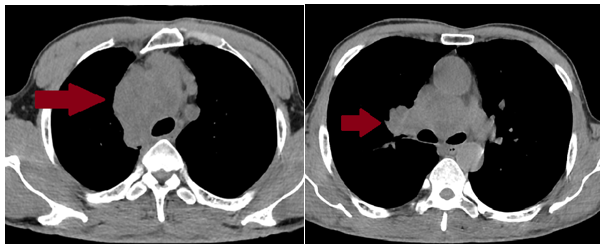

Hình 1. Hình ảnh khối lớn trong trung thất giữa KT 81x63x70mm, xu hướng xâm lấn màng phổi trung thất và nhu mô phổi phải vùng rốn phổi, chèn ép bờ phải khí quản, nhiều hạch trung thất kích thước lớn nhất 34x28mm (mũi tên màu đỏ), nốt đặc thùy trên phổi phải theo dõi thứ phát.

Hình 4. So sánh hình ảnh chụp cắt lớp vi tính lồng ngực của bệnh nhân trước và sau 3 tháng điều trị (các khối trung thất giảm kích thước đáng kể, kích thước lớn nhất 15x25mm – mũi tên màu vàng

=> Bệnh nhân đạt đáp ứng tốt với điều trị: khối u thu nhỏ kích thước đáng kể, lâm sàng được cải thiện rõ rệt. Trong quá trình điều trị, bệnh nhân có xuất hiện một số tác dụng phụ như: mệt mỏi, chán ăn, ngủ kém sau truyền hóa chất 2-3 ngày, ngoài ra chưa phát hiện các tác dụng phụ khác.

Đánh giá theo tiêu chuẩn RECIST 1.1, bệnh đáp ứng một phần (PR – Partial Responce). Hiện tại, bệnh nhân tiếp tục được điều trị phác đồ Atezolizumab - Etoposide - Carboplatin đủ 6 chu kỳ.